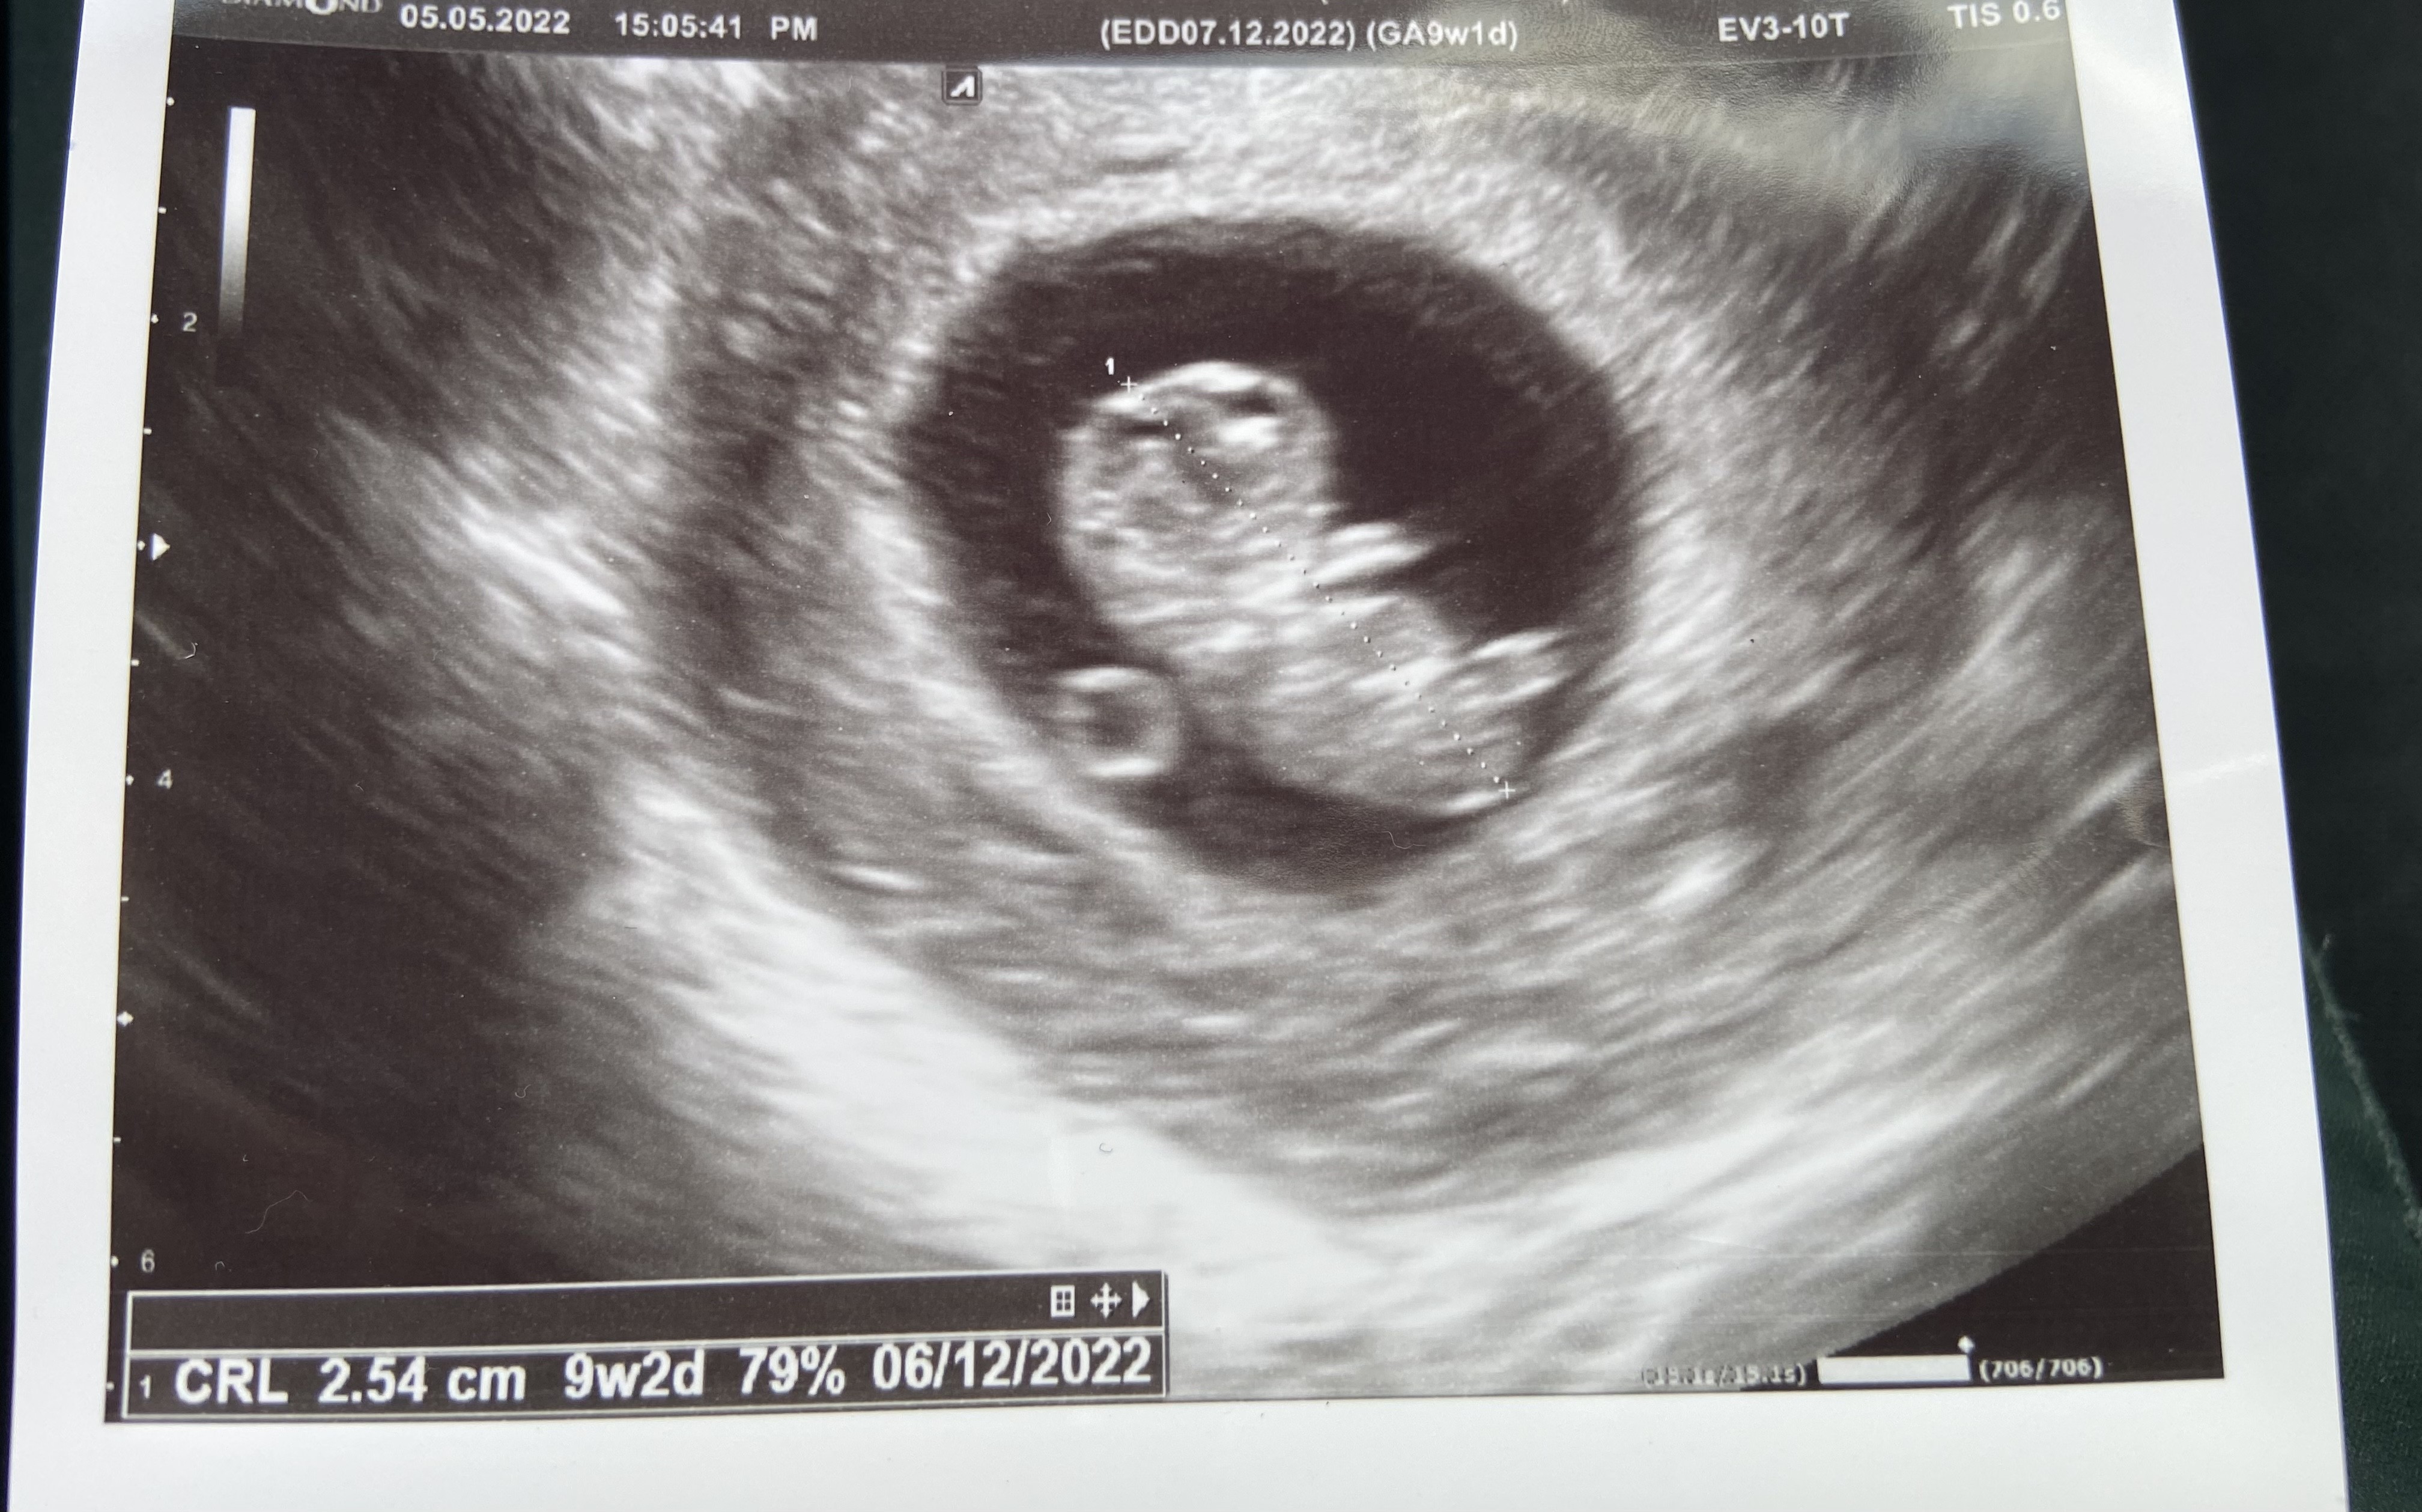

No widzisz mówiłam, że to że objawy ustały to nic nie znaczy, tak samo jak utrzymujące się objawy. Super że wszystko dobrze. Te zdjęcia wszystkie na początku są kiepskie

zaraz se zaczęłam wkręcać że z ciąża może coś nie tak ale mówił mi że wszystko idealnie i nie ma się do czego przyczepić. Chyba że ze względu na wcześniejsze poronienia chce mi oszczędzić tak szybkiego umawiania się żeby potem nie było przykro odmawiać wizyta jak coś.